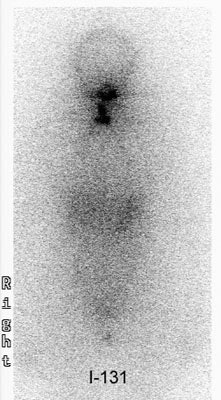

![]() ![]() ![]() |

| Diagnostic scans at 24 hours with 0.3 mCi 123I. No stunning effect is seen on these scans. Images courtesy of Dr. Hee Myung Park. |

| Post-therapeutic scans at 24 hours, and 7 days (last image) with 100 mCi 131I. These scans show excellent uptake of therapeutic dose. Images courtesy of Dr. Hee Myung Park. |